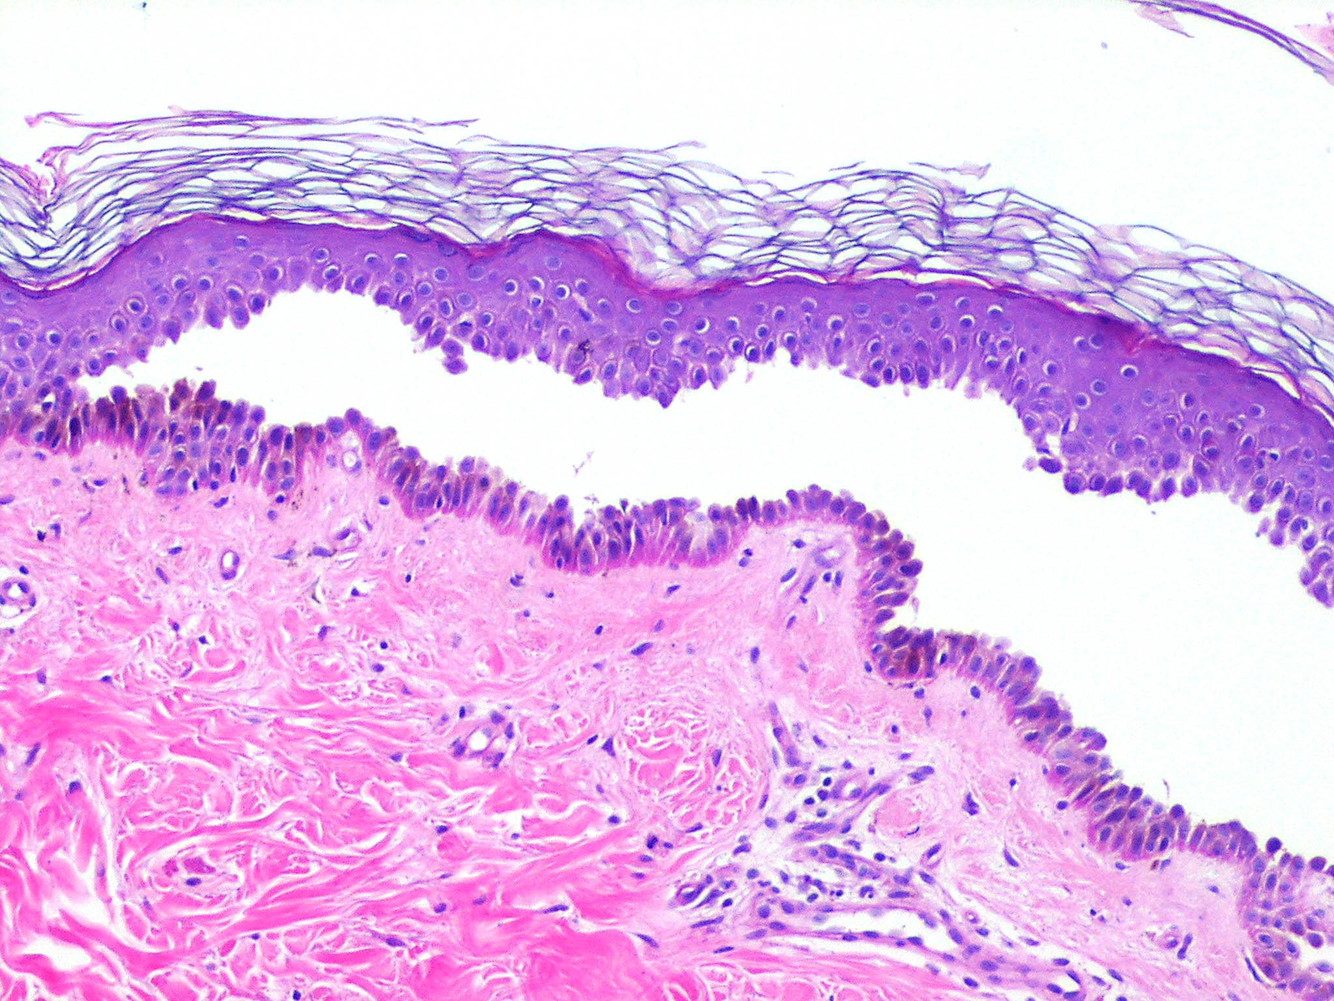

What is this a histology section of?

Bullous pemphigoid